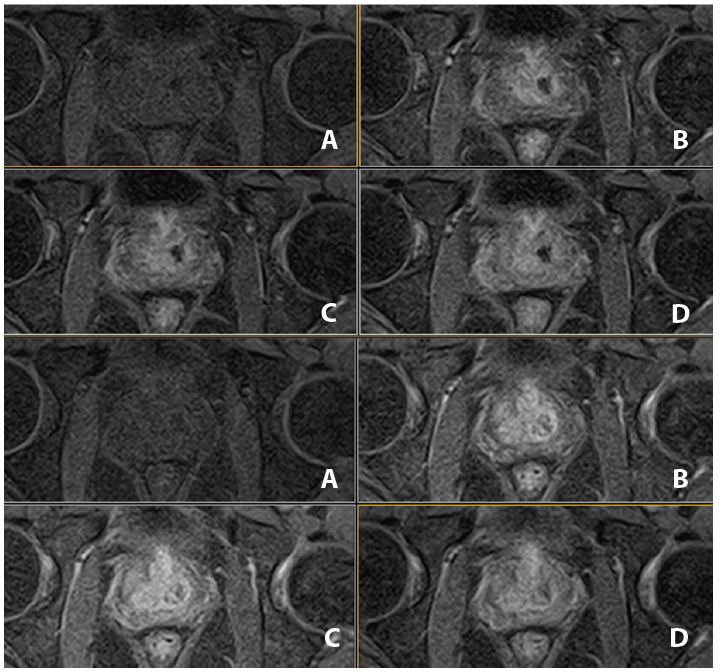

Рис. 14. Аксіальне, Т2-зважене зображне (за протоколом mpMR).

Рис. 15. Aксіальне DWI – A=b0, B=Iso b800, C=Iso b1000 e, D=Iso ADC (за протоколом mpMR)

Рис. 16.  Динаіка. Аксіал (12 фаз)– A=1a phase pre, B=3a phase pos, C=6a phase pos, D=12a phase (за протоколом mpRM).